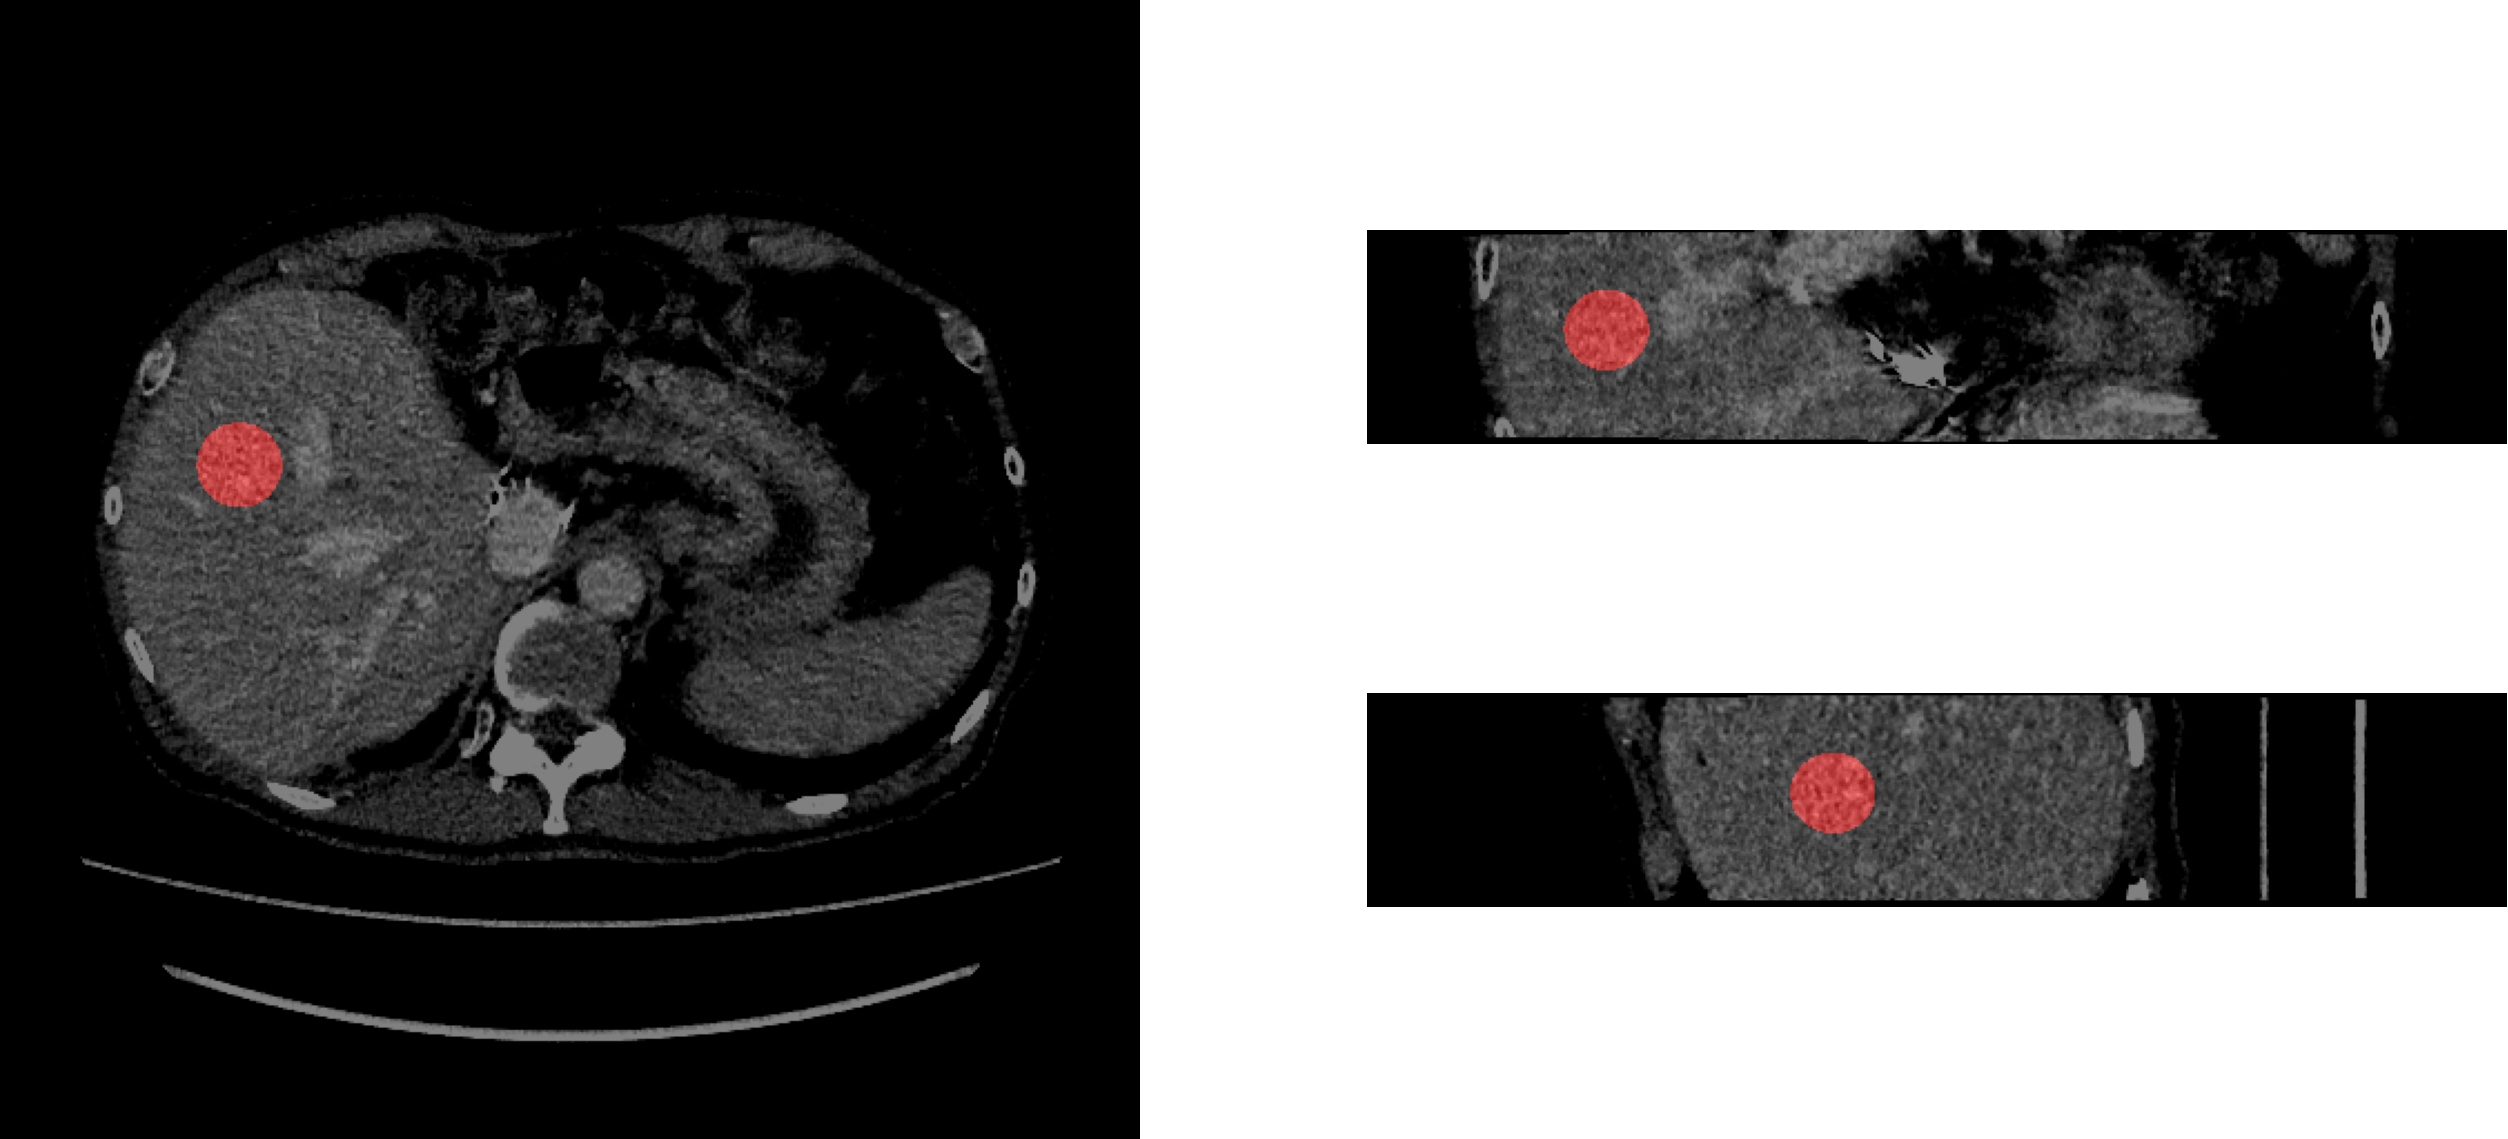

5.2 Regions of Interest

Spherical regions of interest (ROI) of 1.5 cm radius were placed such that their center was 2.5 cm distal to the biopsy needle to ensure that the chosen ROIs were consistent with the corresponding biopsy. An example is presented in Figure 1. This was to ensure that the initial set of ROIs captured a region with a fibrosis stage consistent with that recorded by the biopsy. This is due to the diffuse nature of fibrosis, as the fibrosis stage in a given region of a liver can differ by ±plus-or-minus\pm 1 fibrosis stage.

Refer to caption

Figure 1: Example ROI (left: axial view, upper right: coronal view, lower right: sagittal view).